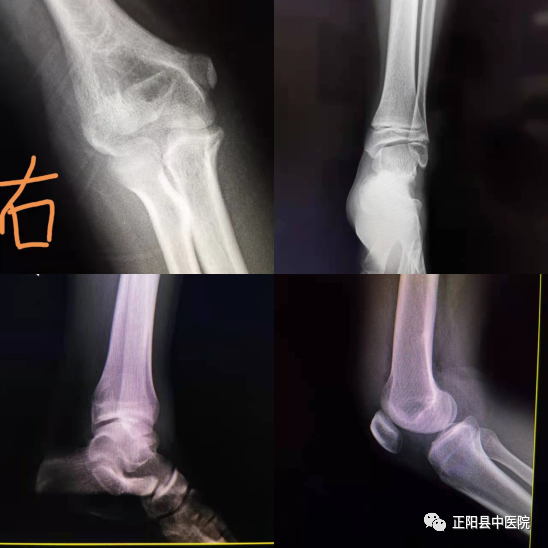

下面我们可以看几个实战中的病例图片(插图〉。在以上的病例中,单凭一张正位片或者是侧位片,你能做出正确的诊断吗?很显然不能达到诊断的目的,会出现漏诊现象。所以在实际工作中,放射科的四肢关节X线摄影技术是有原则性要求的,从众多四肢关节原则中列举几条吧:第一,病人体位要舒适,拍片时需要静止不动,防止产生运动伪影;第二,常规拍片为正位和侧位,最好放于同一张照片上,便于比较。第三,儿童的四肢关节拍片一般需要两侧同时摄影,便于鉴别诊断。如双侧腕关节、双侧膝关节、双侧髋关节等等。